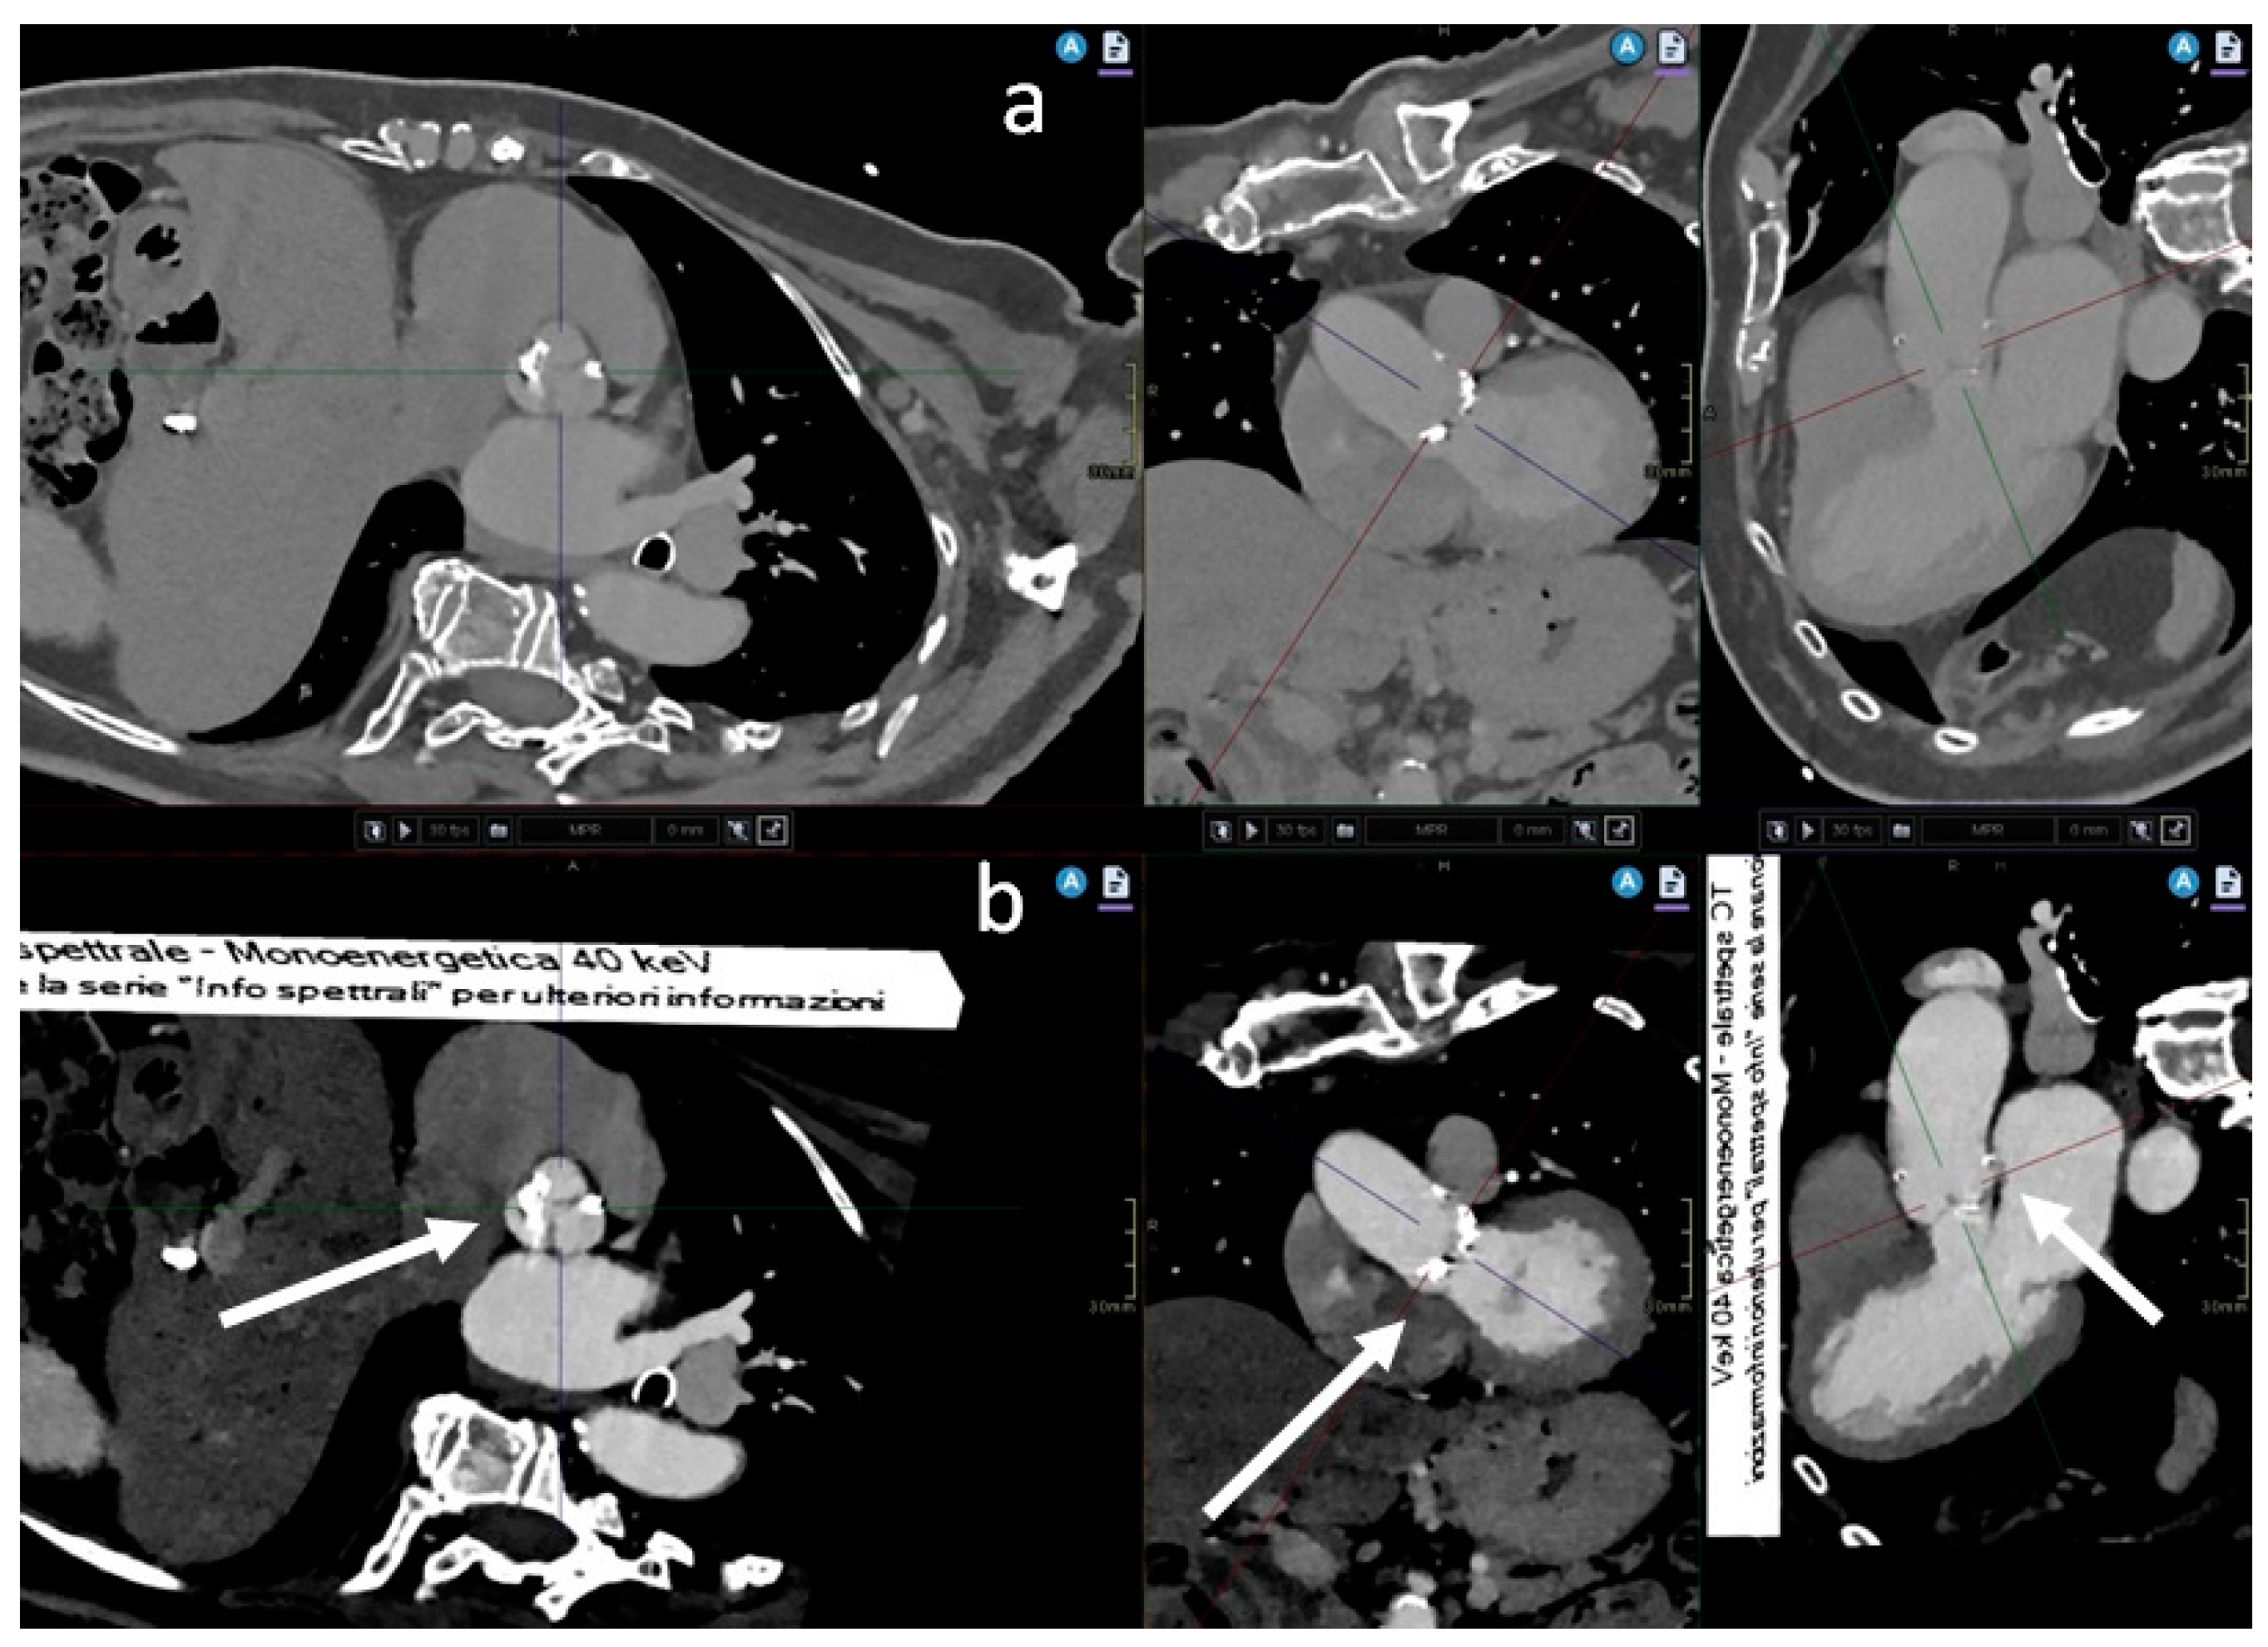

2. Materials and Methods

3. Results

3.2. Quantitative and Qualitative Assessment